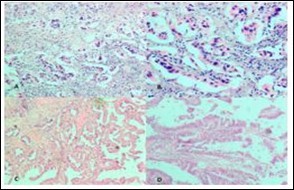

Figure 3.Photomicrograph showing A, Low power view of Adenocarcinoma Gall bladder; B, High power view shows attempted gland formation with moderate pleomorphismmoderately differentiated adenocarcinoma Gall Bladder; C, Low power view of Papillary carcinoma GB; D, High power view showing papillae with fibrovascular cores lined by malignant cells- Papillary carcinoma GB (H&E)

Photomicrograph showing A, Low power                   view of Adenocarcinoma Gall bladder; B, High power view shows attempted gland formation with moderate                  pleomorphismmoderately differentiated adenocarcinoma Gall Bladder; C, Low power view of Papillary carcinoma GB; D, High power view showing papillae with fibrovascular cores lined by malignant cells- Papillary carcinoma GB (H&E)